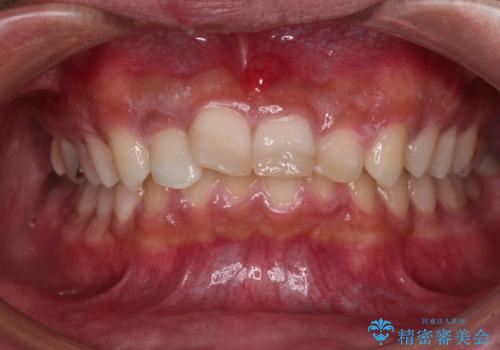

- 酒席の後に転倒して前歯を損傷し、応急処置のみを受けてきたとのことで来院された患者様です。

損傷がひどく、前歯4本と広範囲であったため、症状やレントゲン写真、検査結果が一致せず、定期的に経過を見ながら診断していくこととしました。

右側前歯は歯根が短くなり、パンチング状に歯根に透過像が認められたため、予後不良と判断し抜歯することとしました。

当初のレントゲン写真では根尖部に骨透過像が認められた両サイドの2歯は、歯髄の正常な反応が認められたためそのまま保存し、左側前歯は歯髄が失活していたため根管治療を行うこととしました。

事故直後のレントゲン写真では全ての歯の根尖部に骨透過像が認められましたが、治療後には全ての透過像がなくなっていました。

診断に2-3ヶ月かかりましたが、的確に診断を行うことができました。